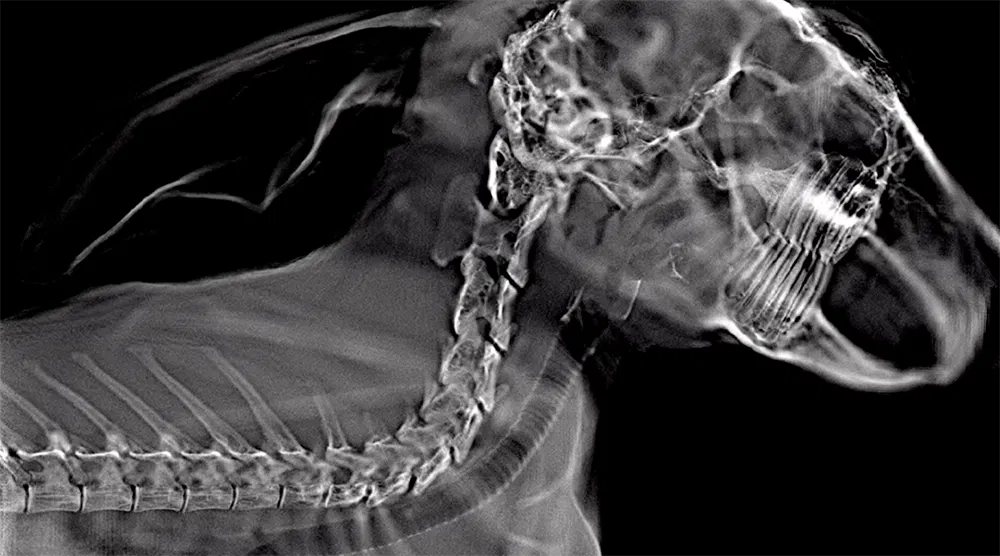

Exotic species often present unique imaging challenges, dense shells, overlapping skeletal structures, and small anatomical features can obscure critical details in traditional 2D X-rays. The Adaptix VetSA3D system uses Digital Tomosynthesis to overcome these limitations, delivering high-resolution, low-dose 3D imaging that reveals hidden anatomy with clarity.

Traditional 2D X-rays often obscure critical structures due to overlapping anatomy, making it difficult to identify underlying issues. Adaptix VetSA3D overcomes this by using Digital Tomosynthesis to produce multiple slices through the body, which allows veterinarians to detect fractures in small or complex bones, identify respiratory and gastrointestinal obstructions, assess shell and spine abnormalities in reptiles, and spot subtle signs of metabolic bone disease with greater clarity.